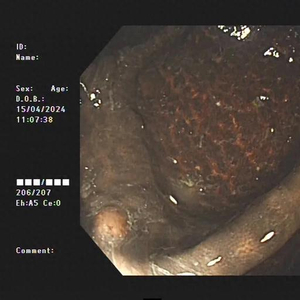

不查不知道,一查吓一跳!患者整条大肠内壁呈现棕黑色蛇皮样的改变,黑色素沉着明显,诊断为“结肠黑变病”,若继续发展,有癌变的可能。

据医生介绍,临床上许多患者自行口服药物后筛查肠镜均有不同程度的结肠黑变病。正常的结肠黏膜就像我们的口腔黏膜一样,是淡红色的,看起来光滑平坦,黏膜表面的小血管纹理清晰可见。而结肠黑变病的肠黏膜色泽呈现棕色、褐色,有豹纹或者蛇皮一样的条状纹,严重的甚至会变成黑色。

结肠黑变病患者

结肠黑变病是因为结肠壁的吞噬细胞吞噬了褐色素样物质,导致肠壁色素沉着。通俗点说,就是大肠吃多了色素,就变成了黑肠。此外,直肠前突、肠套叠、溃疡性结肠炎等其他疾病也可能导致黑变病。